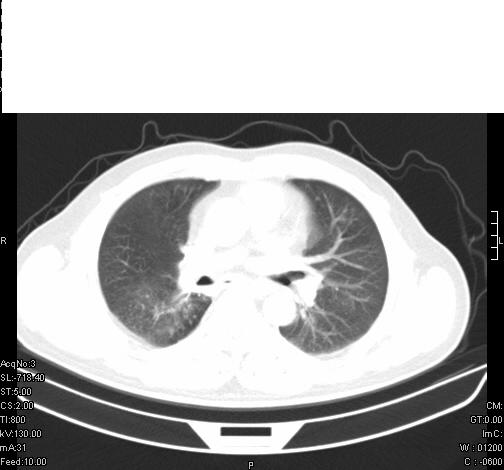

标题: CT6685:右肺阻塞性炎症,增强CT。

前几天,发了患者的平扫片,患者抗炎一周后增强扫描。右中叶病灶吸收明显,但下叶病灶未见明显吸收。右肺门可见结节影,看来凶多吉少

右肺下叶散在的斑片状致密影,下叶支气管变窄。考虑:右肺慢性炎症。

支持:右肺下叶散在的斑片状致密影,下叶支气管变窄。考虑:右肺慢性炎症。

右肺下叶支气管壁不规则增厚,右肺下叶有斑片状影分布。考虑右肺中央型肺癌伴右肺下叶阻塞性改变。建议支纤镜检查。平扫比增强较好显示了病变情况。

既然抗炎治疗有效,可继续治疗;右肺下叶支气管管腔狭窄,管壁增厚,右下肺见斑片状高密度影,右侧主支气管后见结节影(淋巴结?),肺癌不能排出。